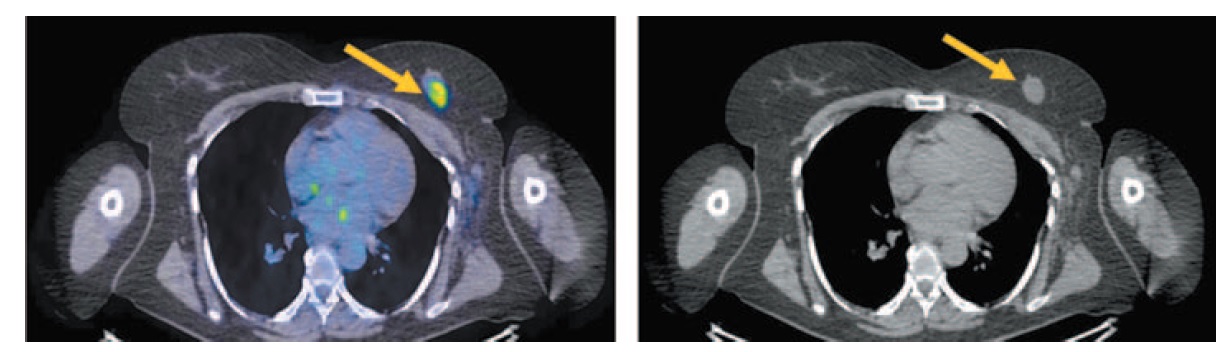

В костях скелета определяются множественные очаги остеобластической перестройки, с повышенной фиксацией РФП (рис. 11).

Рис. 11. Больная К., 55 лет. На сагиттальных ПЭТ/КТ проекциях в костях скелета определяются множественные очаги повышенной фиксации РФП на фоне остеобластической перестройки костной ткани, SUVmax 4,86.

Fig. 11. A 55-year-old woman. Sagittal PET/CT images show that in the bones of the skeleton are defined multiple focal increased RFP uptake against the background of osteoblastic bone remodeling, SUVmax 4.86.